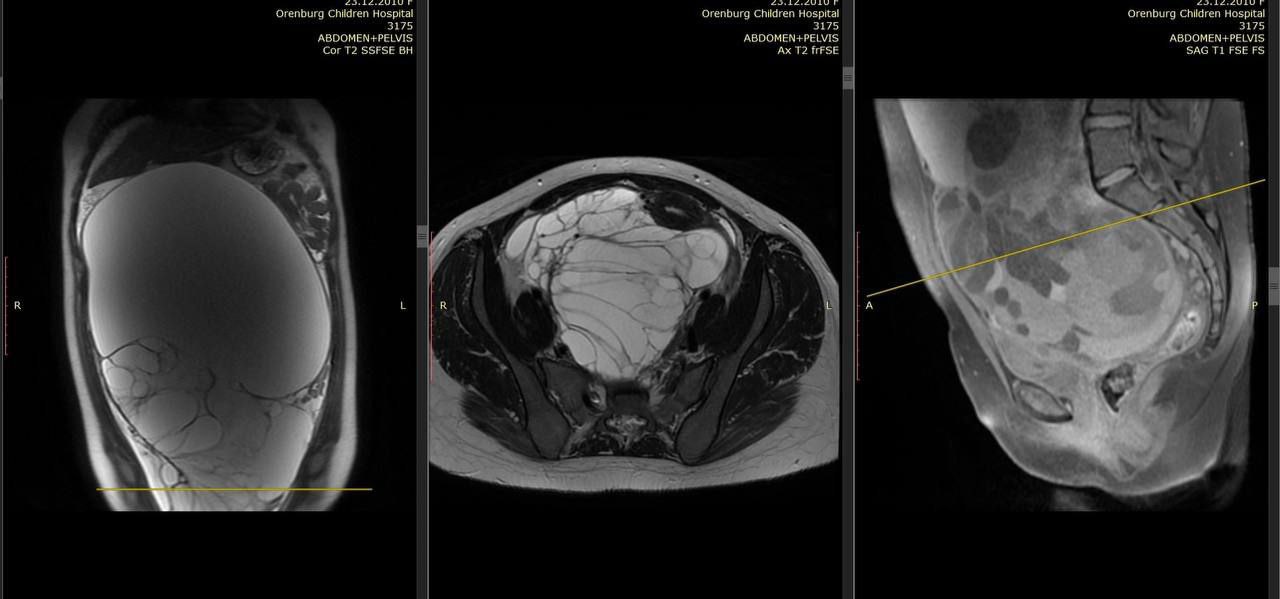

В Оренбурге медики совершили уникальную операцию, в ходе которой была удалена огромная опухоль весом 8 кг у 13-летней девочки. Это событие привлекло внимание не только местных жителей, но и специалистов из других регионов страны.

Хирурги провели сложную операцию по удалению опухоли весом 8 кг.

Операция проводилась в одном из местных медицинских учреждений, где команда хирургов работала над устранением опухоли, которая значительно ухудшала качество жизни пациентки. Врачи отметили, что такие случаи достаточно редки и требуют высокой квалификации и опыта.

Процесс операции длился несколько часов, и, несмотря на сложность, хирурги успешно справились с задачей. После операции девочка находится под контролем врачей, и восстанавливается после проведенного вмешательства.